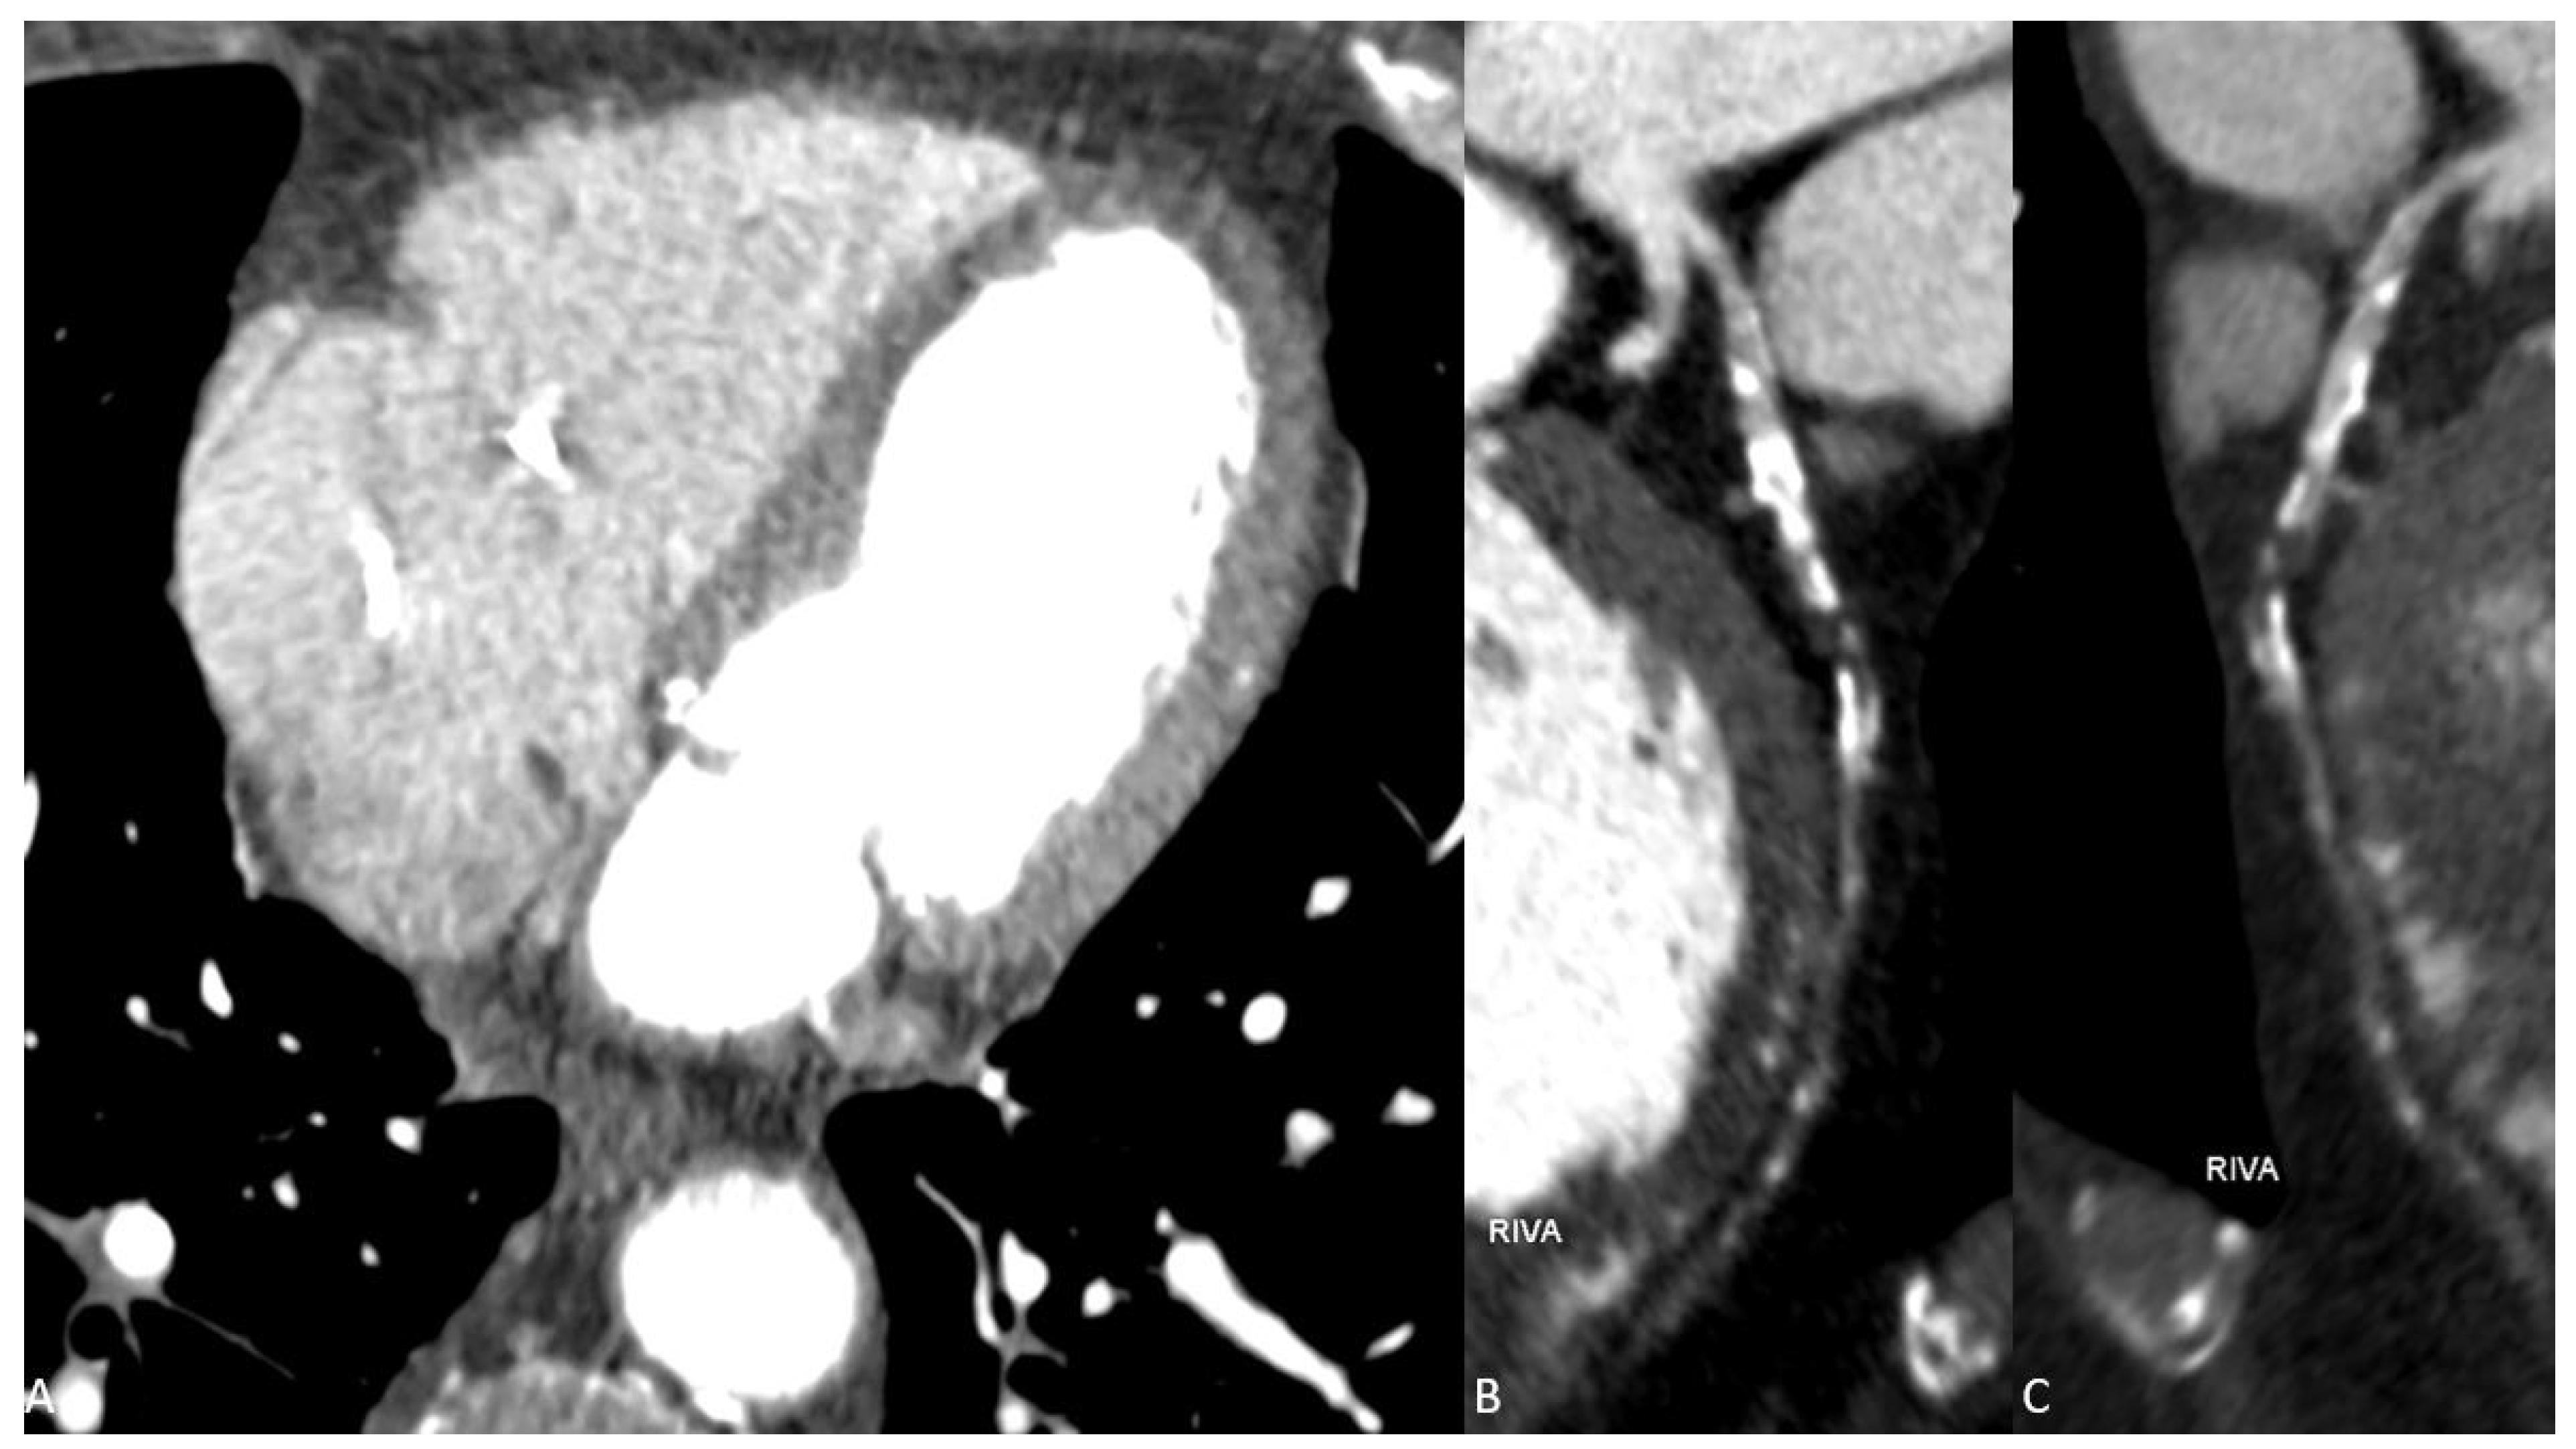

Figure 1. Conventional arterial paratransversal CT series (A) and reconstructions (B,C) show multiple soft and calcified plaques in the LAD (RIVA) in the context of CAD. However, the presence of contrast material in the distal course of the LAD remains questionable and cannot be assessed with high diagnostic confidence by conventional CT imaging due to significant image noise and consecutive low image quality.

We report the case of a 80-year-old man who presented to our emergency department two days after fall and persistent unclear consciousness. The patient’s medical history included a T-cell lymphoma and a high-grade atrioventricular block treated with a heart pacemaker. Except for chest pain, the patient did not report any medical complaints. Clinically, only a small hemorrhage on the face and ear was noted. Therefore, a cranial CT scan was performed to rule out intracranial hemorrhage. The CT scan showed no evidence of intracranial hemorrhage. Instead, significant reduction in brain volume and a fracture of the nasal bone were detected. After ruling out intracranial hemorrhage, further investigations were performed. The laboratory testing showed elevated levels of the following parameters: C-reactive protein, CK, CK-MB, LDH, Troponin T and D-Dimer. The ECG examination presented acute ST-segment elevation in V1 and V2, suggestive of an anterior wall infarction. The patient was hemodynamically stable and presented improvement in respiration after receiving an anti-infective therapy with Rocephin. Beyond that, a significant decrease in inflammatory parameters was observed. Due to chest pain with syncope and suggestive findings in ECG and laboratory tests with positive D-Dimers and myocardial enzymes, an acute coronary syndrome with syncope was suspected. However, neither an acute pulmonary artery embolism nor an aortic dissection could completely be excluded as differential diagnoses in this constellation. Thus, a triple-rule-out (TRO) DECT scan of the chest was performed. The ECG-gated CT examination was performed on a third-generation, dual-source computed tomography (Somatom® Force, Siemens Healthineers, Forchheim, Germany) consisting of a triple-rule-out scan protocol. According to patient weight, 100 mL of 350 mg iodine/mL (Imeron) was injected into a peripheral vein at a rate of 4 mL/s through a double-piston power injection. After an unenhanced scanning, which is an essential part of our standard protocol, an early contrast-enhanced phase was acquired using test bolus scanning in the descending aorta. The late enhancement scan was obtained 7 min after injection of the contrast medium for myocardial assessment. The total radiation dose was 547 mGycm. CT-scan parameters were as follows: tube A had a voltage of 100 kV and tube current of 165 reference mAs and tube B had a voltage of 140 kV and a tube current of 140 reference mAs. Care Dose4D was applied. All contrast-enhanced CT image series were performed in DECT mode and reconstructed using a medium-soft reconstruction kernel (Qr40f) with a 0.5 mm section collimation in a 0.5 mm increment in the axial, coronal and sagittal planes. In addition, a weighted mix of DECT reconstructions from the 100 kV and 140 kV image data (with a tin filter) were generated to simulate conventional 120 kV images (simulated 120 kV) in all planes. DECT image series were post-processed on a DECT workstation (syngo.via, version VB10B, Siemens Healthineers) to generate virtual monoenergetic images at 55 keV and iodine maps using default settings. While the conventional CT series demonstrated multiple soft and calcified plaques in the left anterior descending (LAD) artery with questionable presence of contrast media in the distal course (Figure 1), the VMI series at 55 keV clearly showed a total LAD occlusion (Figure 2).